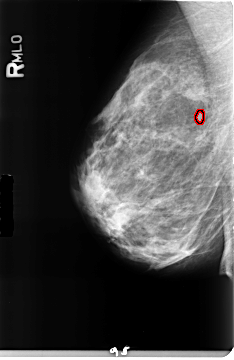

ics_version 1.0 filename B-3157-1 DATE_OF_STUDY 9 6 1997 PATIENT_AGE 42 FILM FILM_TYPE REGULAR DENSITY 2 DATE_DIGITIZED 5 5 1998 DIGITIZER LUMISYS LASER SEQUENCE LEFT_CC LINES 4720 PIXELS_PER_LINE 2928 BITS_PER_PIXEL 12 RESOLUTION 50 NON_OVERLAY LEFT_MLO LINES 4736 PIXELS_PER_LINE 2704 BITS_PER_PIXEL 12 RESOLUTION 50 NON_OVERLAY RIGHT_CC LINES 4704 PIXELS_PER_LINE 2800 BITS_PER_PIXEL 12 RESOLUTION 50 OVERLAY RIGHT_MLO LINES 4672 PIXELS_PER_LINE 3032 BITS_PER_PIXEL 12 RESOLUTION 50 OVERLAY |

FILE: B_3157_1.RIGHT_MLO.OVERLAY TOTAL_ABNORMALITIES 1 ABNORMALITY 1 LESION_TYPE MASS SHAPE LOBULATED MARGINS CIRCUMSCRIBED ASSESSMENT 4 SUBTLETY 4 PATHOLOGY BENIGN TOTAL_OUTLINES 1 BOUNDARY |